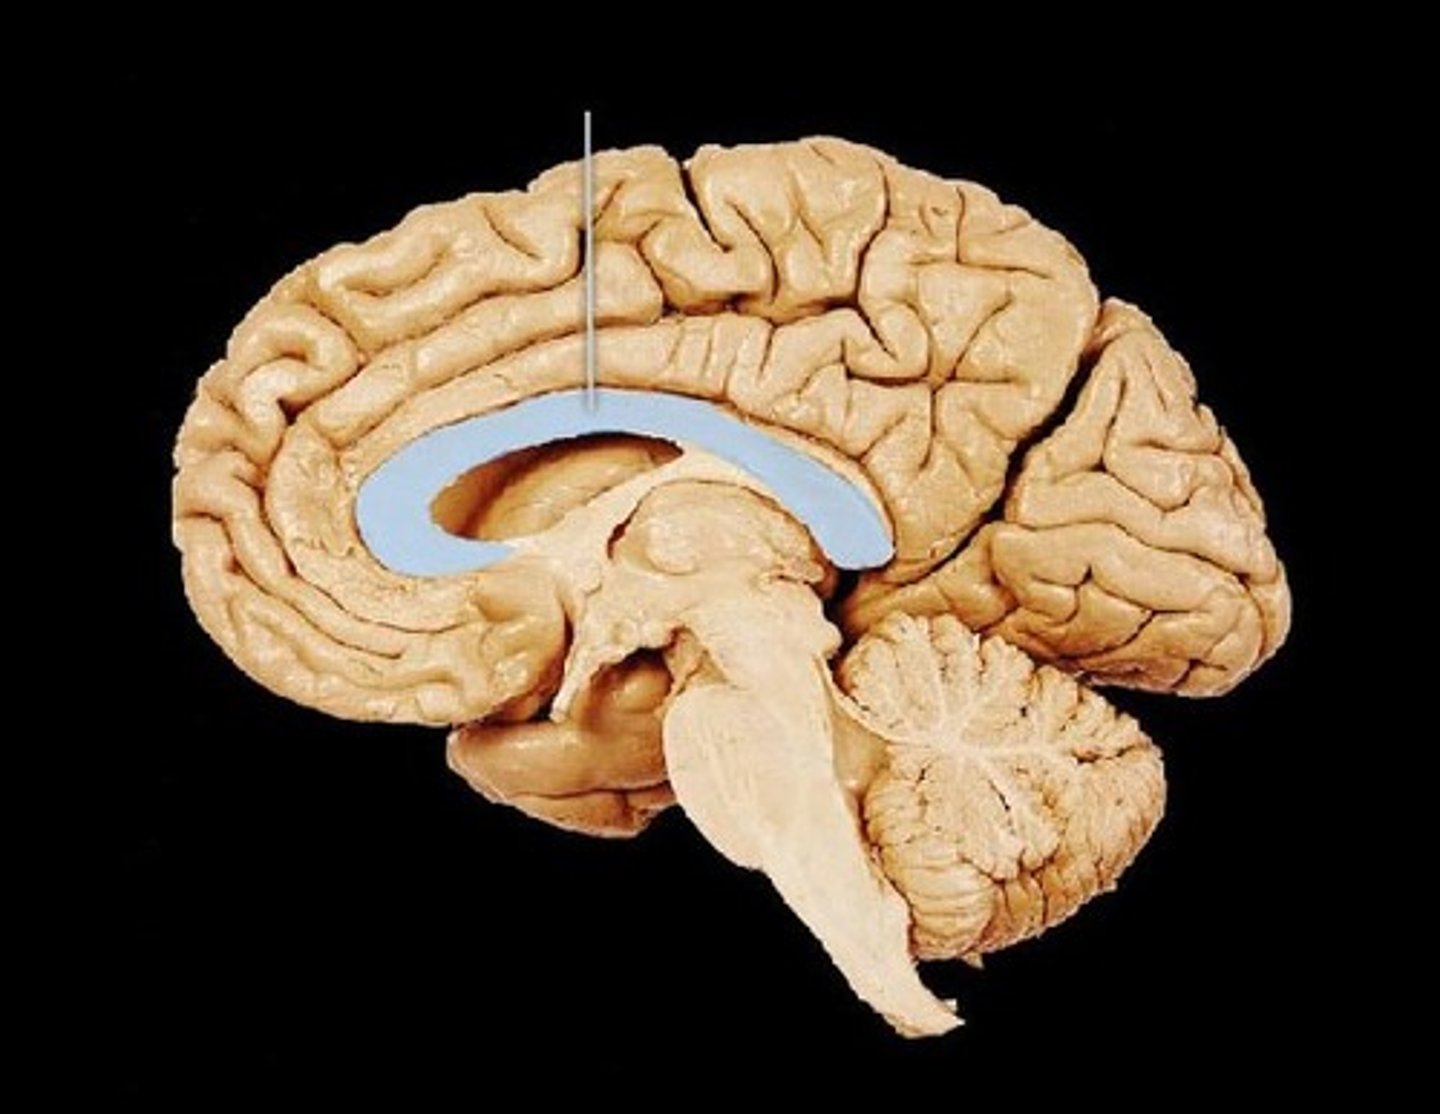

Corpus callosum

structure, first sombrero

Cingulate gyrus

ridge, bigger sombrero